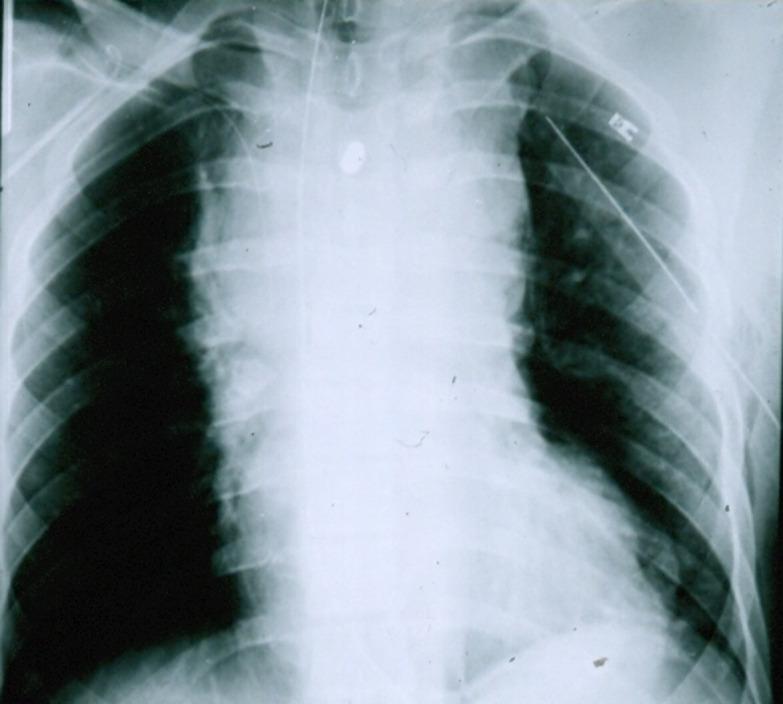

https://cdn.ncbi.nlm.nih.gov/pmc/blobs/ee89/7745519/fbb84769dc3d/tsaco-2020-000658f01.jpg